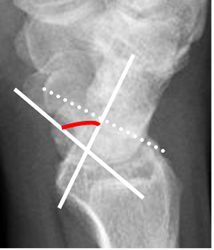

Fig 74. Inestabilidad tipo DISI.

A: Rx lateral. Angulo escafolunado mayor de 60.